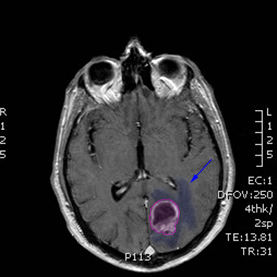

Όγκος εγκεφάλου με περιβάλλον οίδημα. |